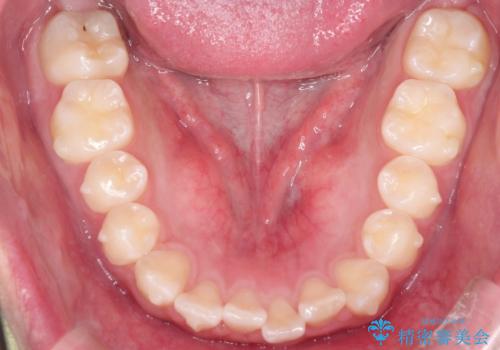

目立たずに矯正を終えることができ、患者様にも満足していただきました。